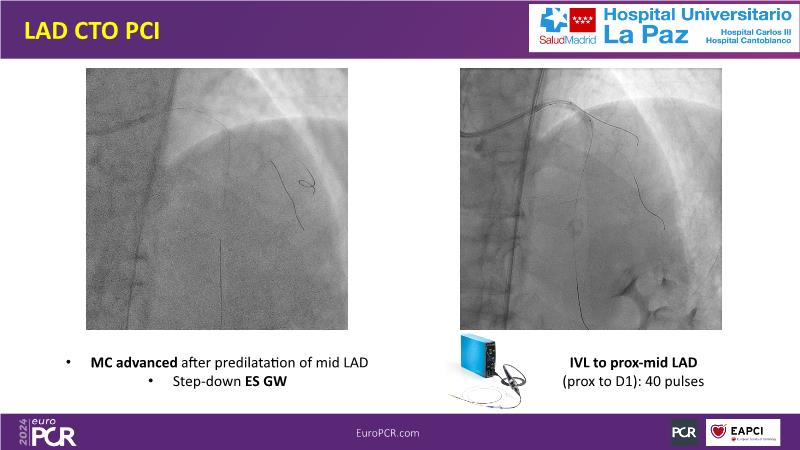

Explore this session to uncover the common association between calcium and acute coronary syndrome, and how intravascular lithotripsy (IVL) offers a safe solution for calcified lesions, with comparable procedural success rates. However, note that ACS cases involving calcium may lead to higher major adverse cardiac events (MACE). Special attention is warranted for women due to their propensity for adverse outcomes. Discover how the C2 + IVL catheter enhances procedural flexibility, yet high intracoronary imaging rates did not yield differences in MACE. Additionally, learn about the potential role of IVL in treating in-stent restenosis (ISR).

- To share clinical experience to uncover practical tips and techniques for intravascular lithotripsy in complex calcified lesions